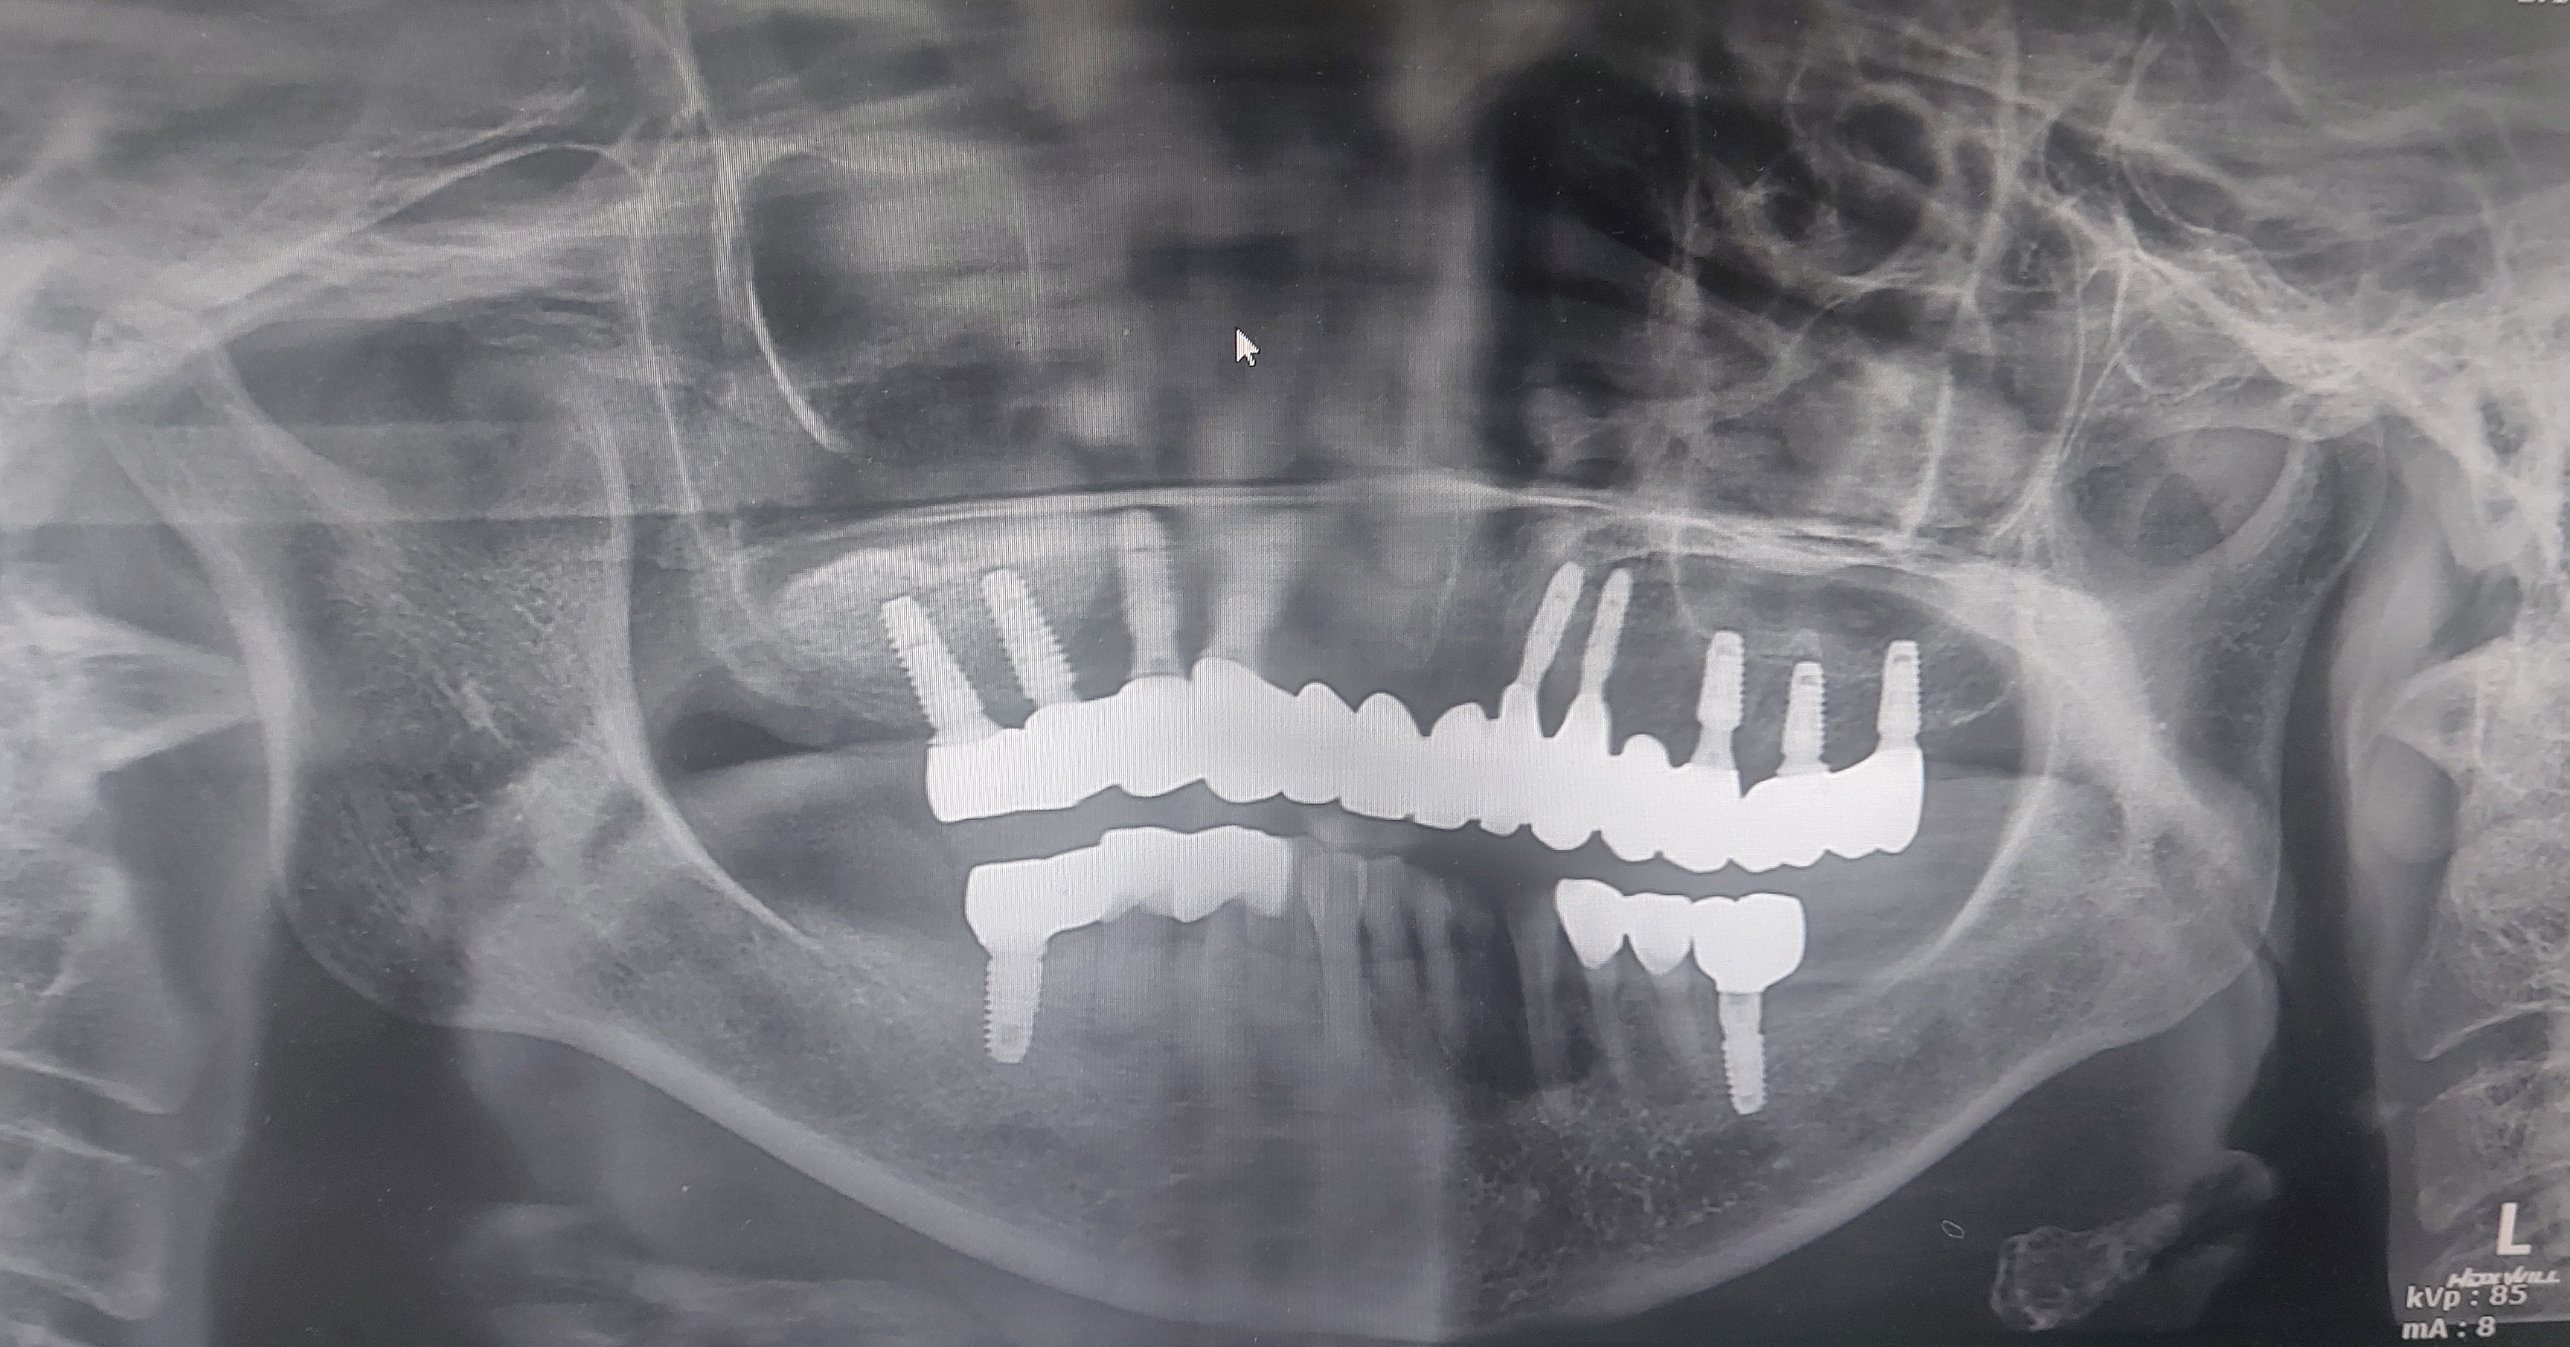

최종 완성후 마지막 교합조정을 하였습니다. 환자분이 잘 사용하고 계셔서 기분이 좋았습니다.

초진때 환자분과의 충분한 대화를 통하여 진료의 방향을 정합니다.

이번 증례는 골질의 조건이 좋지않고 환자분 또한 골다공증약을 드시고 계시기에 정확히 원칙에 준하여 아주 단계적으로 진행하였습니다. 어려운 증례였지만 환자분이 약 10달간의 긴 시간동안 잘 협조해 주셔서 잘 마무리 지을수 있었습니다.

( 물론 빠른 완성도 가능하였지만 임시치아 기간을 충분히 가져서 가장 편한 교합상태를 찾은 후에 완성된 증례입니다.)

=== > 골질이 좁은 환자의 상악재건 임플란트가 잘 마무리 되어서 포스팅합니다.